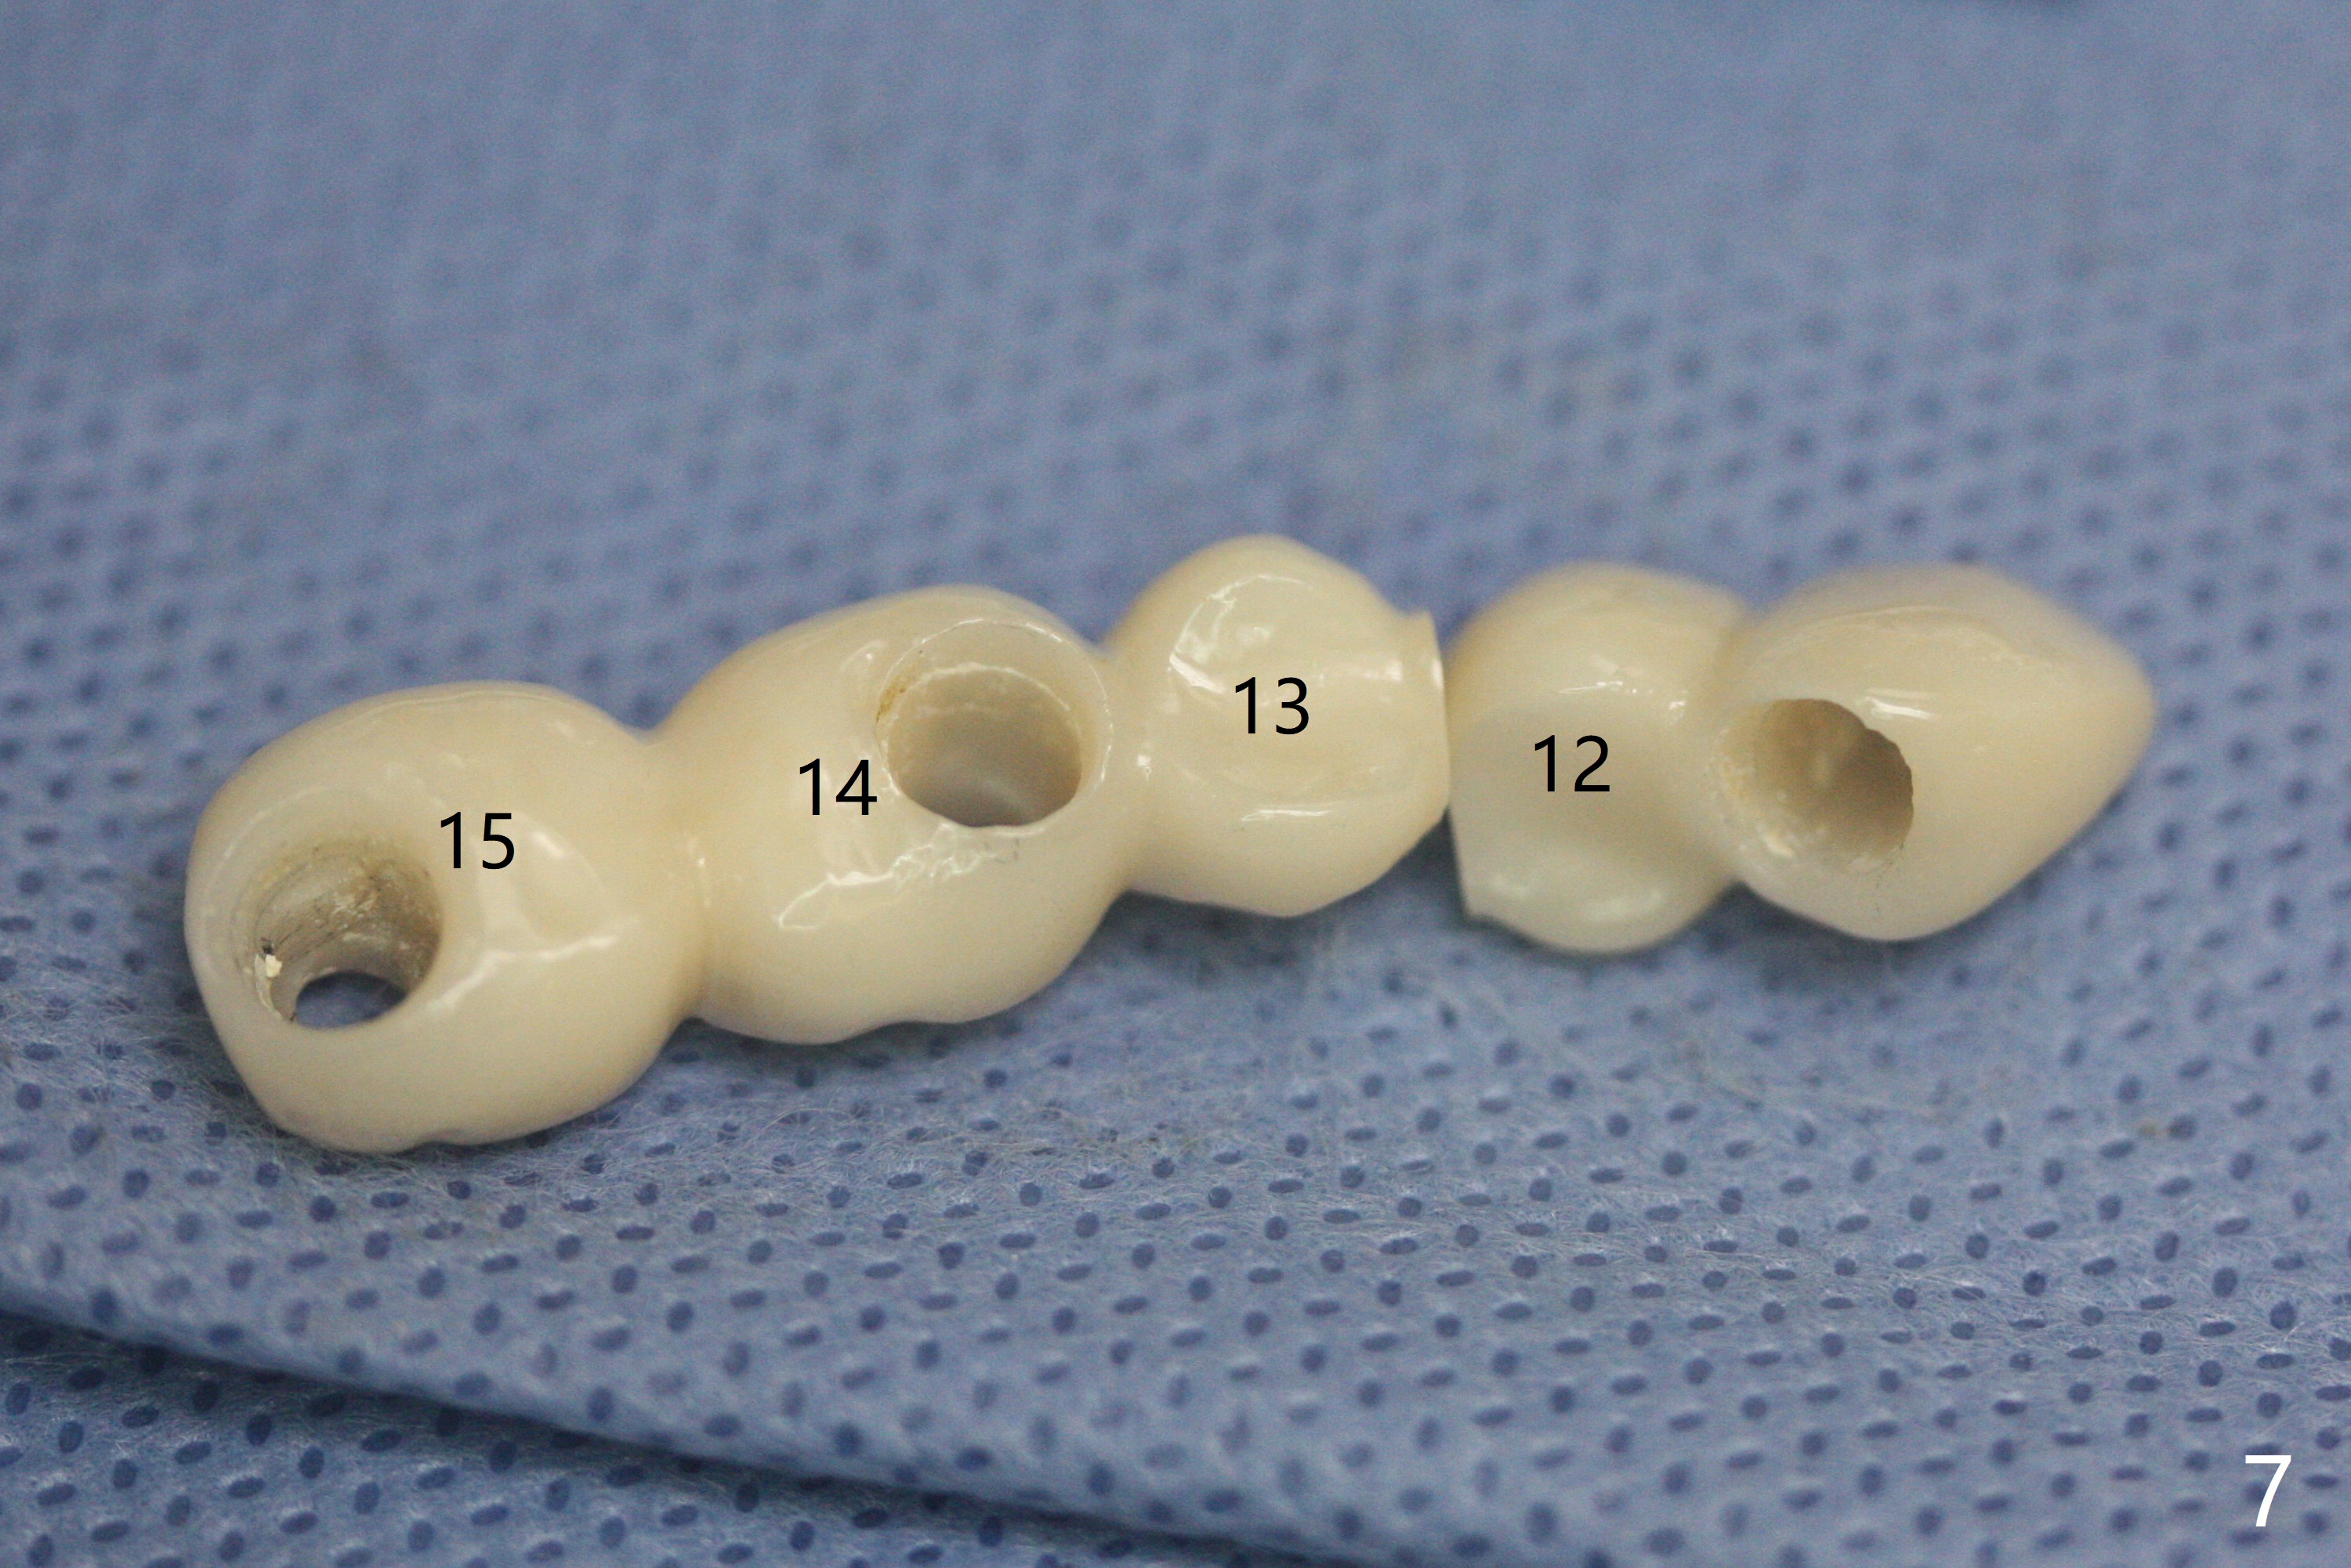

A 48-year-old man returns to clinic with fractured FPD 1 year 5 months post cementation (temp bond, Fig.1,7). It appears necessary to add an implant at #13 site (Fig.2). The narrow ridge is reduced to start an osteotomy (Fig.3 *). After change in osteotomy position and trajectory (Fig.4), a 3x10(4) mm 1-piece implant is placed (Fig.5). With deeper placement of the implant (Fig.6 arrow), cortical bone graft is placed (*).